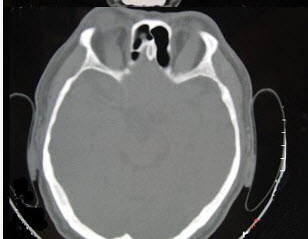

女性50岁,消瘦、多饮多食,脖子粗大,双侧眼球突出,一年余,CT检查如图所示,应考虑为()。

A、眼型格氏病

B、甲状腺眼病

C、炎性假瘤

D、横纹肌肉瘤

E、眶部结核

B